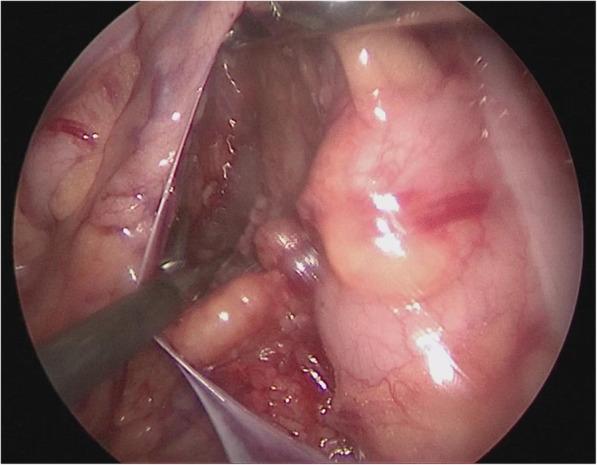

A modified technique of single-incision laparoscopic hepaticojejunostomy for children with choledochal cysts.

To present a modified laparoscopic surgical technique that works to optimize the surgical view in laparoscopic total excision of choledochal cyst in pediatric patients.

METHODS

From June 2015 to June 2017, a total of 48 pediatric cases of choledochal cyst were admitted. Their age ranged from 15 month to 8 years (average 3.5 years). The Todani types were: type I (n = 32) and type IVa (n = 16), according to the diagnostic criteria of ultrasound, abdominal computed tomography (CT) and magnetic resonance cholangiopancreatography (MRCP).

RESULTS

Total cystic excision with hepaticoenterostomy was accomplished laparoscopically in 48 cases with our transumbilical single -incision method without conversion to open surgery. Average duration of operation was 200 min (range 170-240 min), average intraoperative blood loss was 9 ml (range 6-14 ml) without the need for blood transfusion. The 72-h postoperative ultrasound reported no abdominal effusion, when the intraperitoneal drainage tube was removed. There was no postoperative complication during the 6 months of follow-up.

CONCLUSIONS

We accomplished the same postoperative outcome in laparoscopic total cyst excision with our modified method as that with conventional laparoscopic surgery. This technique allows the operator to have a stabilized surgical view without needing to rely on an assistant to hold up the liver lobe for larger operative space.